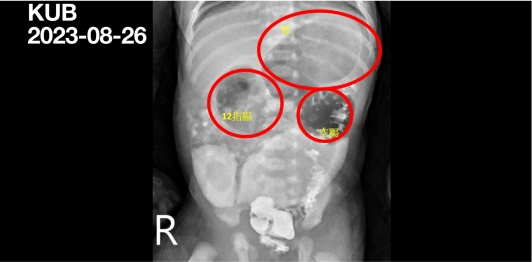

圖:透過腹部X光攝影檢查,可以明顯看見因為腸道閉鎖造成的腸胃道腫大。